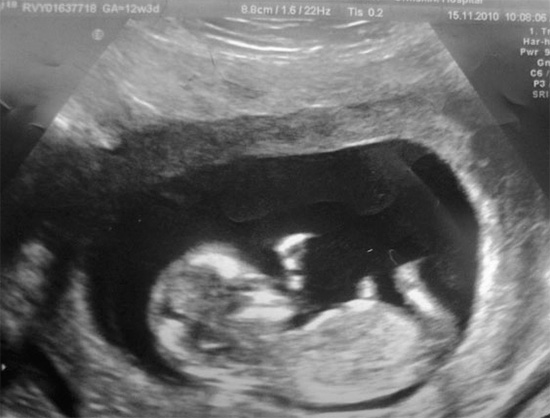

Di norma, il trattamento della carie secondaria durante la gravidanza, specialmente se la patologia procede in forma cronica, i dentisti preferiscono non condurre fino all'inizio del secondo trimestre. È nelle prime 12-13 settimane che vengono posati tutti i sistemi di organi del feto e il rischio di effetti negativi dei farmaci su questo periodo è massimo, anche se è ancora piccolo. A partire da 14-15 settimane, l'uso di anestetici speciali consente di eseguire la riabilitazione in sicurezza.

Tuttavia, la probabilità di ciò è estremamente ridotta: attraverso la barriera placentare, i batteri riescono a penetrare solo in casi estremamente rari.e gli abitanti della cavità orale non hanno praticamente alcuna possibilità di sopravvivere nei tessuti dell'embrione e di esercitare alcuna influenza su di esso. Queste abilità sono principalmente possedute da virus. Ma, come nel caso di qualsiasi malattia infettiva, la presenza di carie nelle donne in gravidanza comporta una serie di procedure igieniche e un'attenta cura orale.